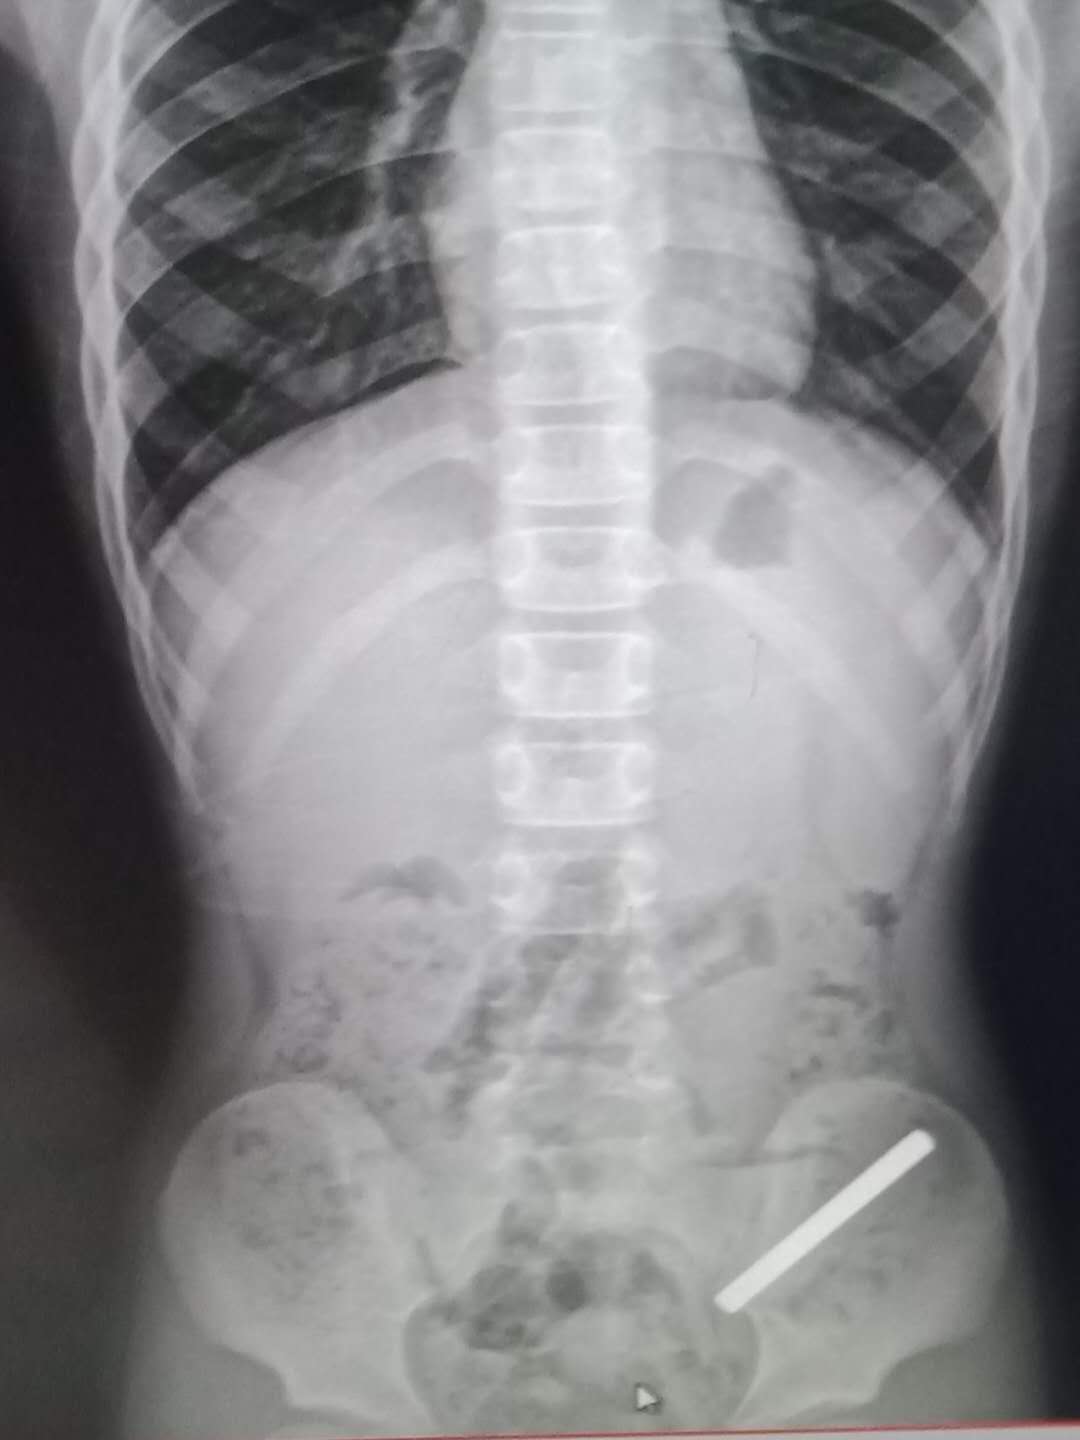

第二天一大早,我便急匆匆的把儿子带去医院做检查,当看到拍片出来的照片里,那枚足足有一根手指那么长的小铁棍斜插在儿子的肠道里时,我吓得冷汗直飚。

而医生的话更是让我心惊胆战,医生说:铁棍太长了,很难排出来的,也有可能会戳破肠道,如果排不出来就要开刀动手术。